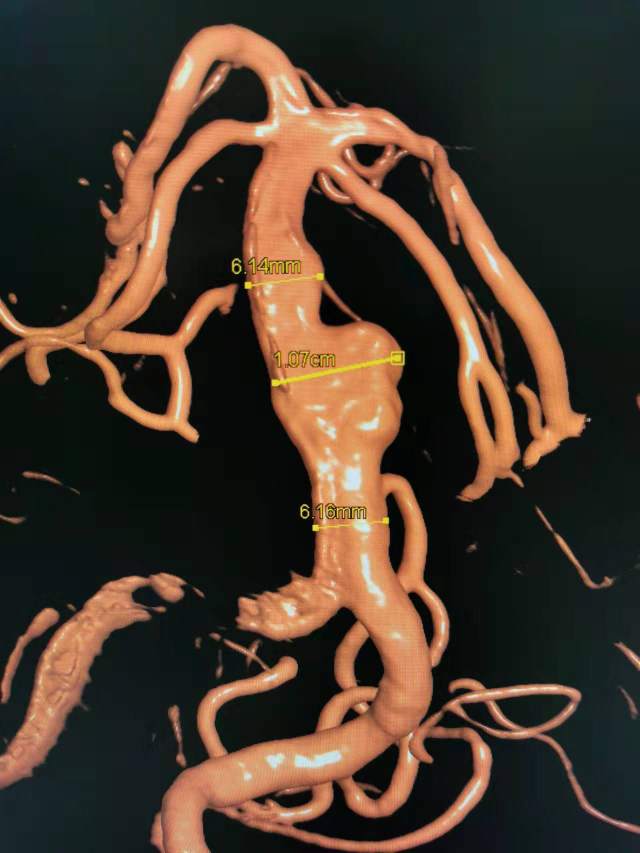

患者男性,34岁,年前自新疆坐车48小时来到我院,诊断:椎基底动脉冗长扩张症,出现脑干压迫症状、后组颅神经症状、部分中组颅神经症状、小脑症状、颅内压增高(220mmHg),症状进行性加重,最大径15mm,血管外面存在血栓造影只能窥见部分,短短两周,病变形态出现明显变化,局部出现明显瘤样凸起(图2-3),手术方案只能临时改变,植入血流导向装置,术后看病人语言、四肢活动均正常,围手术期仍然是一个艰巨的过程,充满了不确定因素,希望患者能安全度过围手术期,早日康复,重返工作岗位~~~